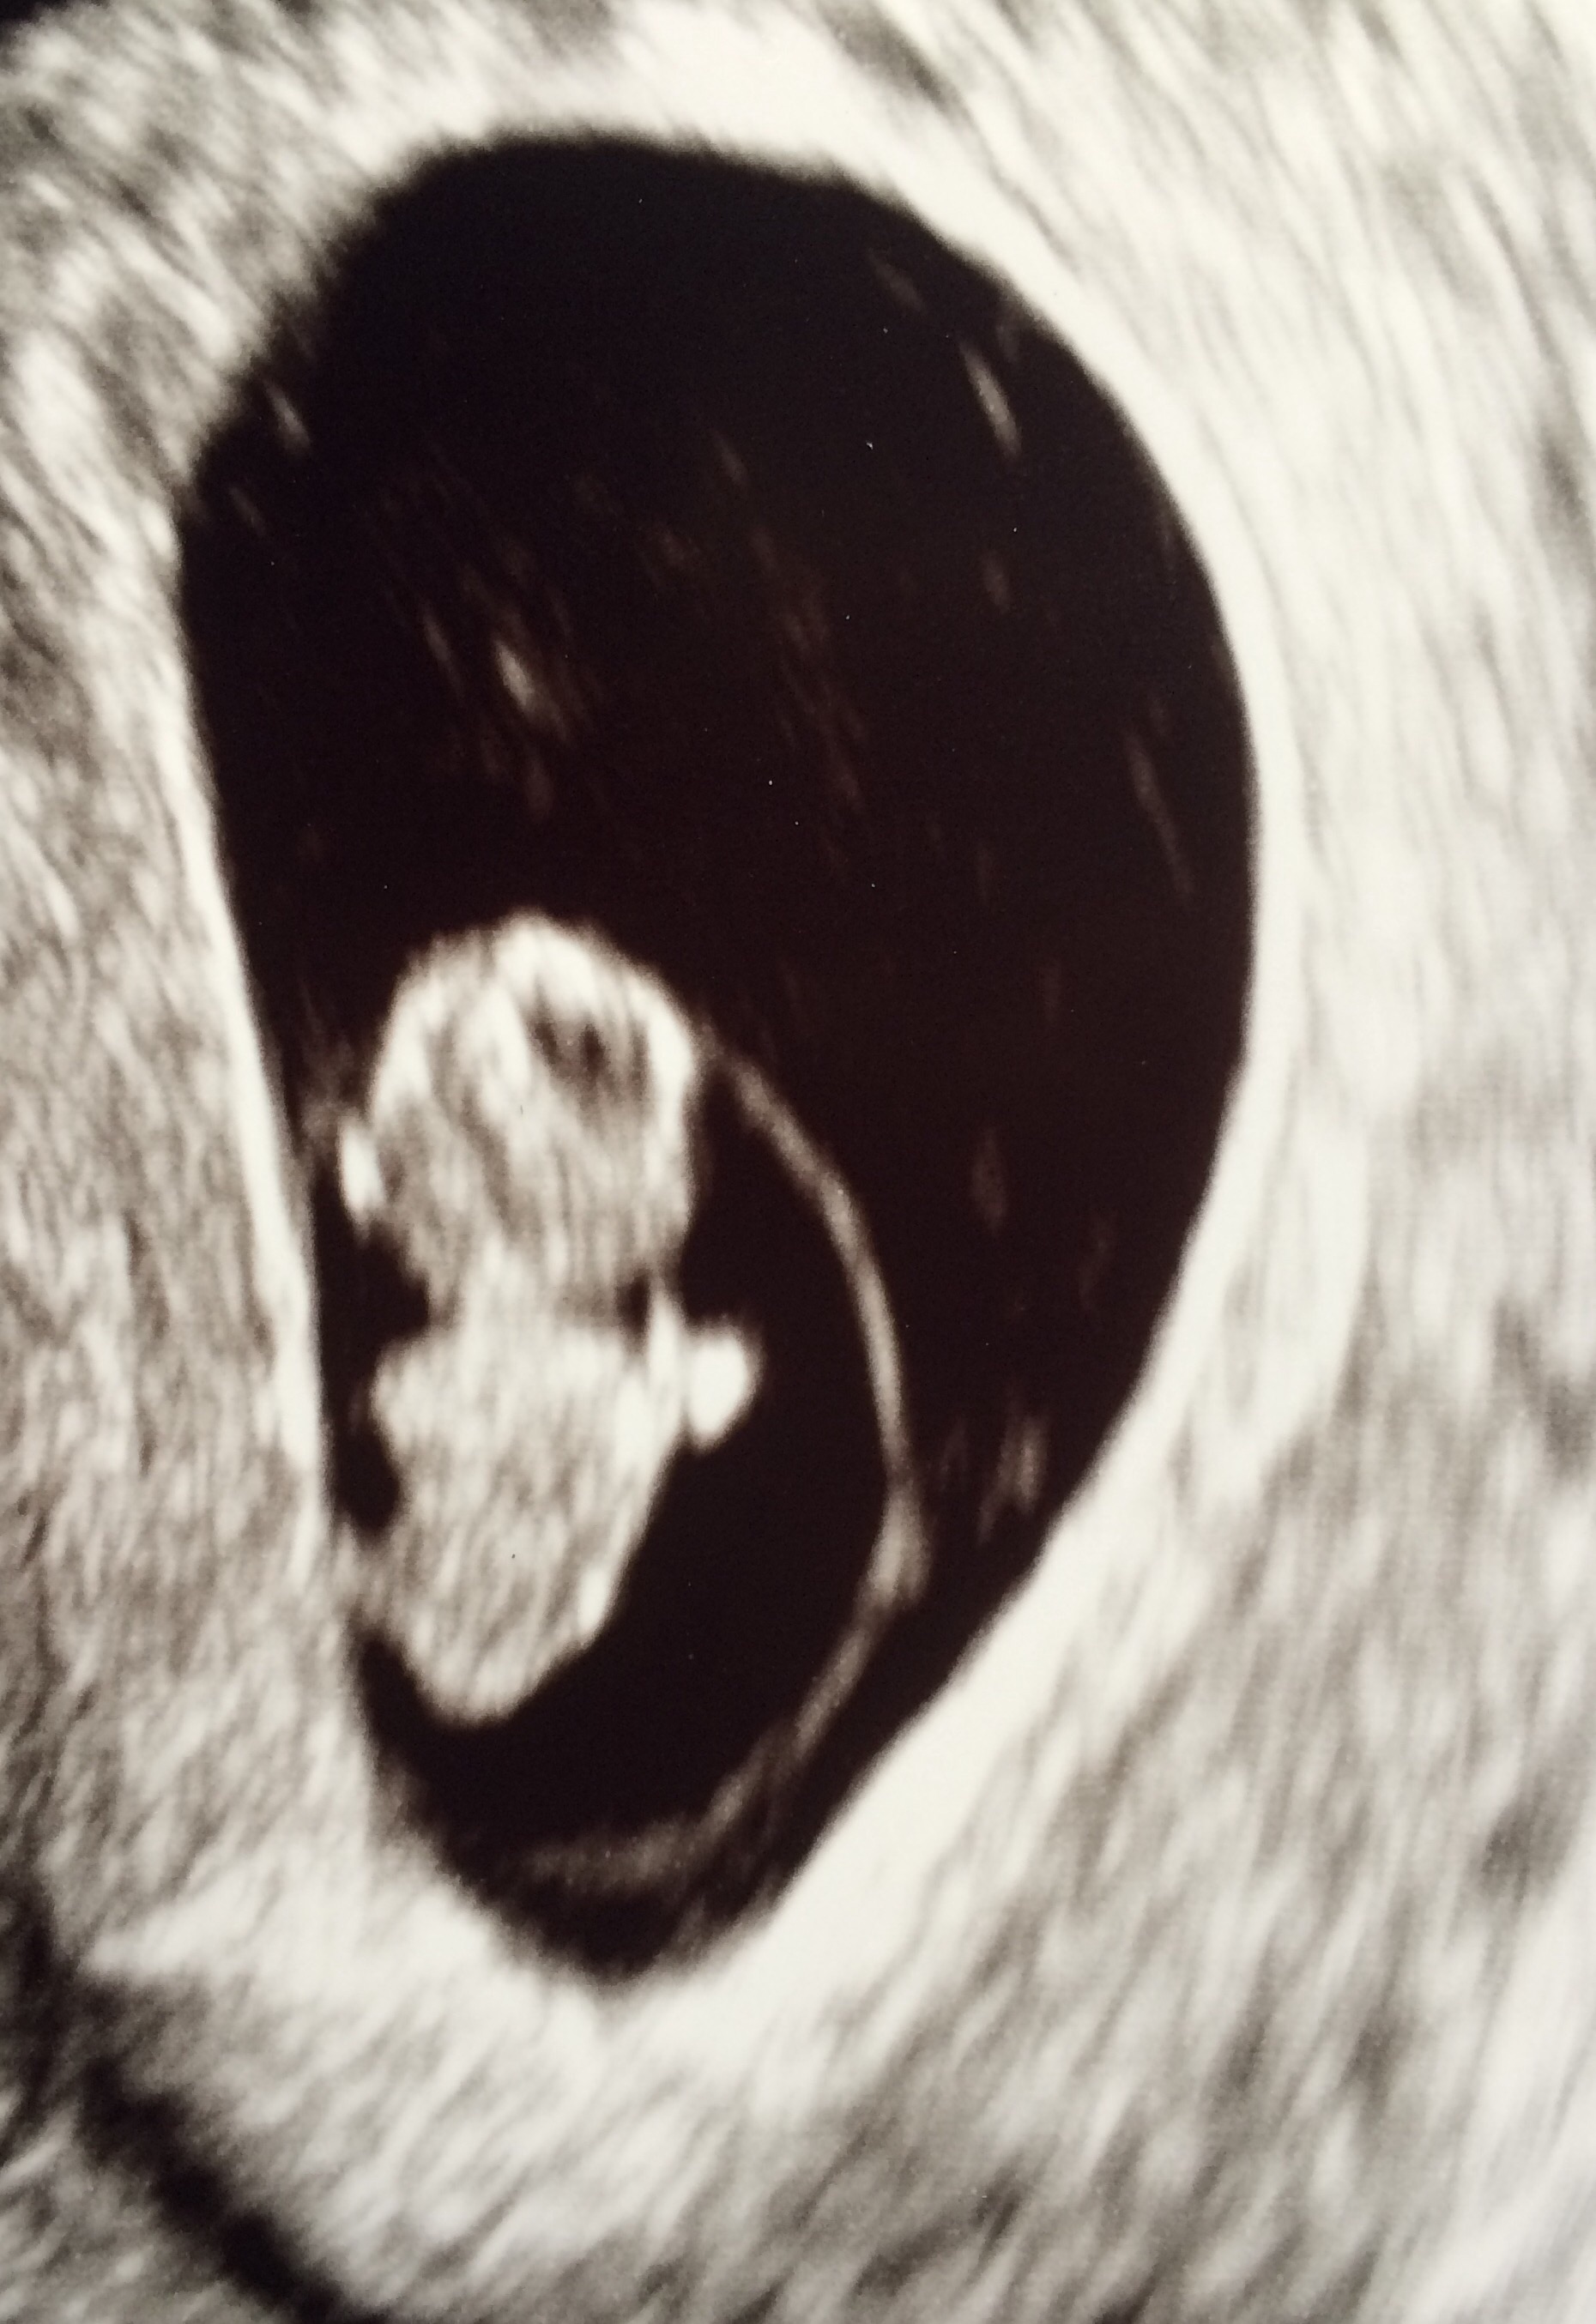

• Had our second ultrasound today, 9w1d. Heart rate was up to 166 this time, we even got to see the baby wiggle around. It's absolutely nuts to see the difference two weeks can make, we could actually make out arms, legs and head this time!